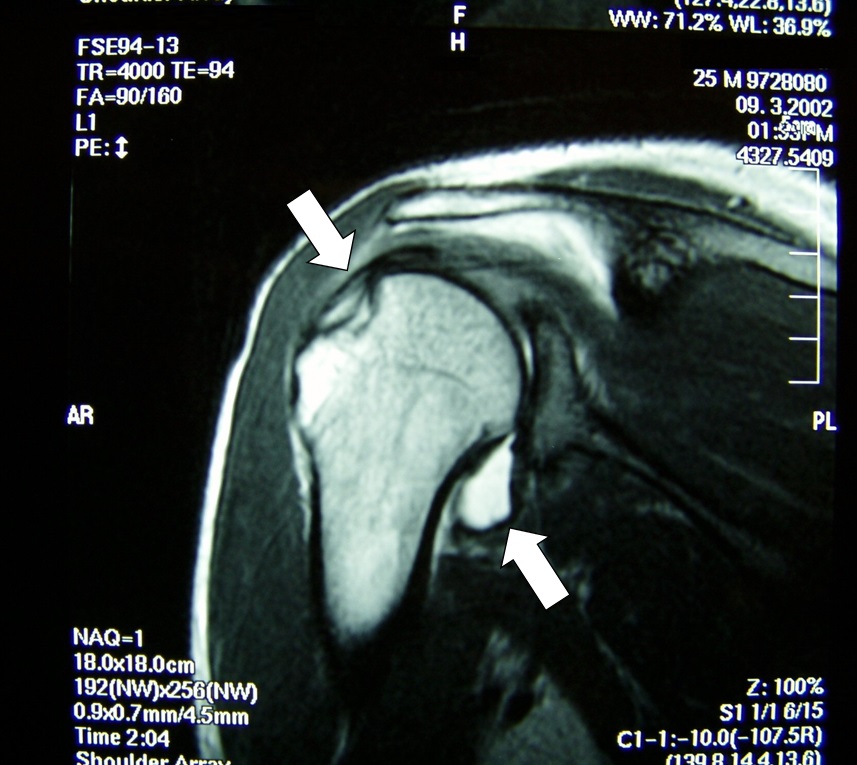

関節のMRI 第3版 | 上谷雅孝, 青木隆敏, 神島 保, 江原 茂, 杉本。肩関節のMRI−読影ポイントと新しい知見−第3版 | 佐志 隆士。その他検査(関節・軟骨) 肩MRI | AIC八重洲クリニック。ホテイ やきとり缶詰 岩下の新生姜入りしょうが味 70g×9缶セット 非常食。【裁断済】\r肩関節のMRI 改訂第3版\r佐志隆士、秋田恵一 編集\rメジカルビュー社\r\r・こちらで購入させて頂いたものです。\r・裁断済みです。そのため、状態は悪いとしています。\r 裁断済みの意味が分かる方のみ、ご購入をお願いいたします。\r・書き込み、マーカーはないと思いますが、確認漏れがあった場合はご容赦ください。\r・スキャン後ですので、多少のヨレやローラー痕がある可能性があります。ご理解の上ご購入をお願いいたします。\r・即購入OKです。\r 恐れ入りますが、値下げ交渉はご遠慮下さい。。肩関節脱臼に対する治療 | 長野整形外科クリニック。その他検査(関節・軟骨) 肩MRI | AIC八重洲クリニック。m3電子書籍 | 関節外科 2022年11月号 Vol.41 No.11 腱板断裂治療。肩関節疾患 | ならやまと整形外科 スポーツクリニック。肩関節(MRI): 正常解剖学 | e-Anatomy。肩関節脱臼|SPORTS MEDICINE LIBRARY|ザムスト(ZAMST)。Open Bore 3T MRIと320列面検出器CTの最新臨床応用 Toshiba 3T。肩関節(MRI): 正常解剖学 | e-Anatomy。プライマリケア医にとってMRIは、確定診断をサポートするための